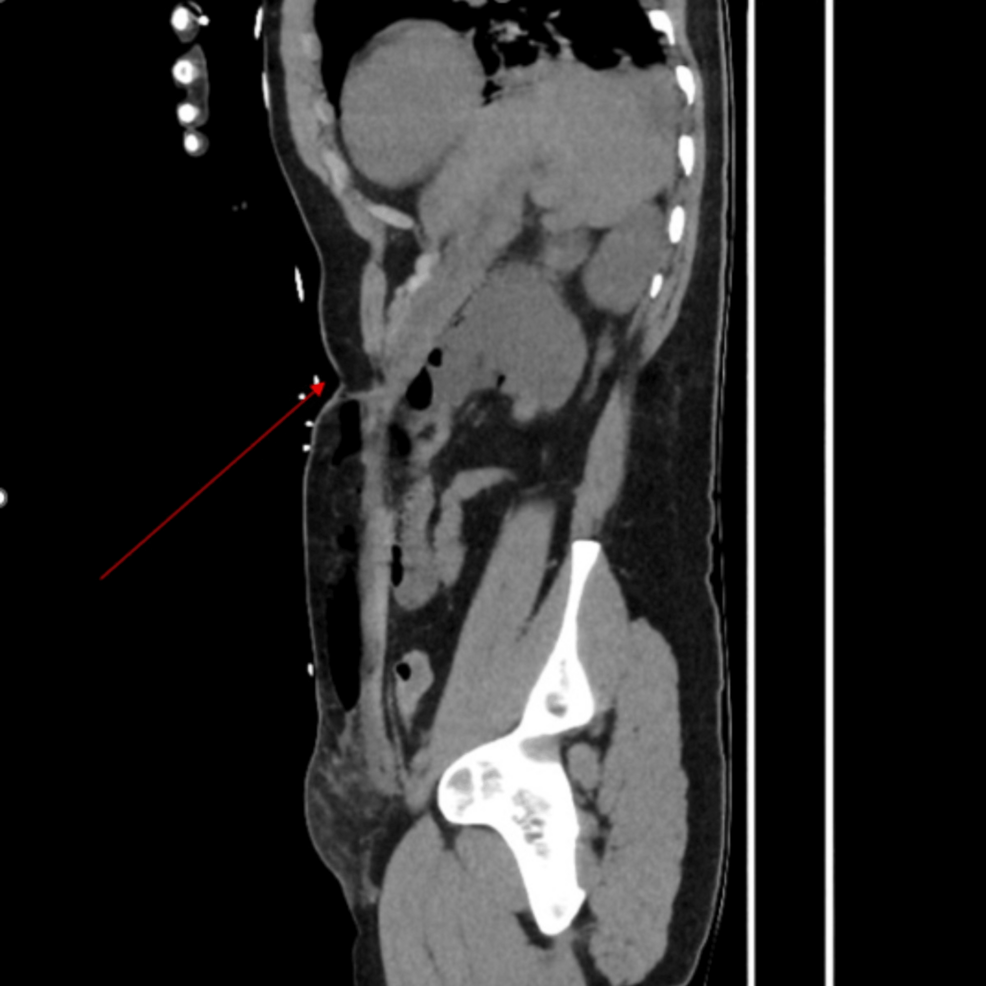

Un caso clínico reciente publicado en Cureus detalla la perforación gástrica subcutánea aguda que ocurrió en el sitio de una gastrostomía endoscópica percutánea (PEG) previa. La complicación se presentó en un paciente sin historial reciente de manipulación o trauma en el área de la PEG.

La gastrostomía endoscópica percutánea (PEG) es un procedimiento común utilizado para proporcionar alimentación a largo plazo a pacientes que no pueden alimentarse por vía oral. Si bien generalmente es seguro, existen complicaciones potenciales, incluyendo la perforación gástrica. Este caso destaca la posibilidad de una perforación gástrica aguda, incluso en ausencia de eventos traumáticos recientes.